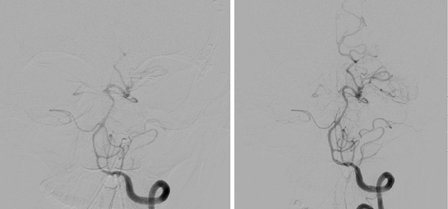

O vasoespasmo se desenvolve entre os dias 4 e 14 após a HSA e é observado na angiografia em 50% a 70% dos casos. Metade desses pacientes desenvolve deficits isquêmicos tardios (DIT) secundários à redução do fluxo sanguíneo cerebral (FSC) regional ou geral.[194] Se não tratado, o DIT evolui para um infarto cerebral permanente em 50% dos casos. Os deficits isquêmicos também podem ser observados na ausência de vasoespasmo angiográfico distinto. Acredita-se que isso se deva, em parte, à autorregulação alterada de vasos cerebrais distais, microtrombos em tais vasos e/ou despolarização de disseminação cortical.[195] Os fatores de risco para o DIT são mau estado geral no momento da admissão, quantidade e duração da exposição ao sangramento subaracnoide, acúmulos de sangue espesso nas cisternas e fissuras, sangue intraventricular e duração da ausência de consciência.[176][181][196][197][198] Embora a presença de sangue no espaço subaracnoide seja necessária para o desenvolvimento de vasoespasmo, a clipagem cirúrgica, durante a qual a maioria do sangue subaracnoide é lavado, parece não oferecer menos risco de vasoespasmo em relação à embolização endovascular com molas.[199][200][Figure caption and citation for the preceding image starts]: Vasoespasmo grave da artéria carótida interna esquerda distal e das artérias cerebrais média e anterior proximais antes (A) e depois (B) da infusão intra-arterial de nicardipino e da angioplastia transluminal com balãoCortesia do Dr. Salah Keyrouz; usado com permissão [Citation ends].

Técnicas endovasculares, como a angioplastia transluminal com balão e vasodilatadores intra-arteriais, reverterão o estreitamento arterial, apesar da melhora clínica não ser consistente.[214][215] A ASA/AHA recomenda que, nos pacientes com HSAa e vasoespasmo grave, a angioplastia cerebral pode ser razoável para reverter o vasoespasmo cerebral e reduzir a progressão e a gravidade da ICT.[37] Existem algumas evidências que dão suporte à angioplastia precoce (dentro de 2 horas desde o início dos sintomas) para proporcionar uma melhora clínica sustentada.[216] Idade avançada e estado neurológico precário na apresentação são preditivos de um desfecho clínico desfavorável após a angioplastia.[217] O nimodipino enteral, um antagonista do canal de cálcio, é administrado para a profilaxia do vasoespasmo.[37] Ele reduz o risco de um desfecho desfavorável e de isquemia secundária após a HSA aneurismática.[218][219]